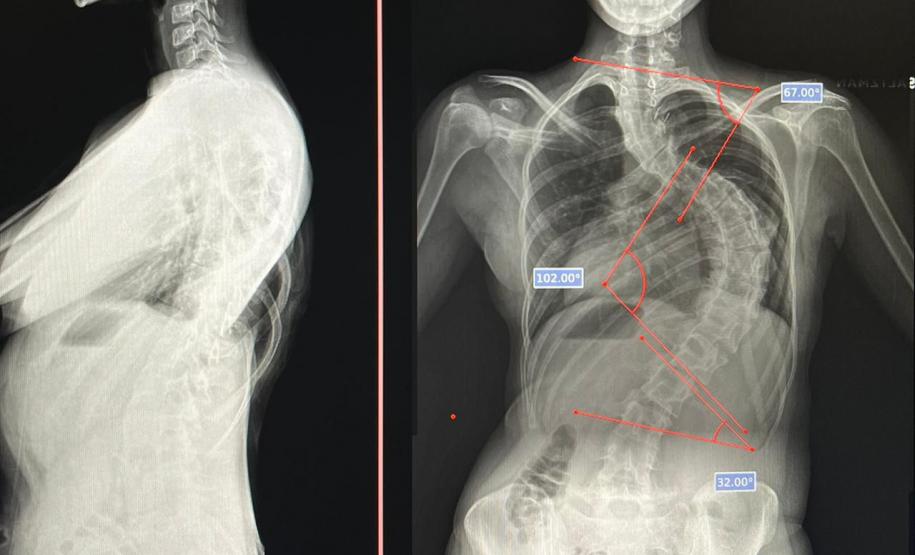

Aos 14 anos, a adolescente Milena de Andrade Carvalho, moradora de Guaratuba, no Litoral do Estado, foi diagnosticada com escoliose idiopática. Sem causa definida, esse tipo de escoliose pode surgir a partir dos quatro anos até a adolescência e ocorre durante o estirão de crescimento. Quando a condição da curvatura ultrapassa os 40 graus, a escoliose se torna progressiva e o paciente continua entortando. Essa condição ocorre com maior frequência em meninas e é muito importante que os pais estejam atentos a qualquer sinal do problema.

“Descobrimos a escoliose por acaso, nunca tínhamos percebido a deformidade, até que um dia ao amarrar meu biquíni, minha mãe observou que eu estava com a coluna torta e ao passar a mão percebeu a curvatura. Decidimos então procurar atendimento médico e tive o diagnóstico da doença já com 50 graus de curvatura e indicação imediata de cirurgia”, contou a adolescente.